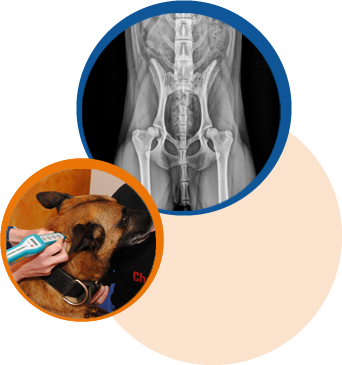

- Skeletterkrankungen

z.B. Hüftgelenks- und Ellenbogendysplasie, Wirbelsäulenerkrankungen, OCD, Frakturen sowie Patellaluxation - Degenerative Erkrankungen